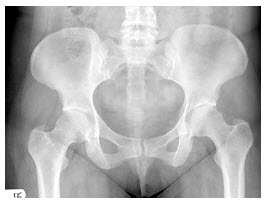

181、多项选择题 左心房增大可见于()

A.动脉导管末闭

B.单纯继发孔型房间隔缺损

C.膈上型完全性肺静脉异位引流

D.室间隔缺损

E.三尖瓣畸形